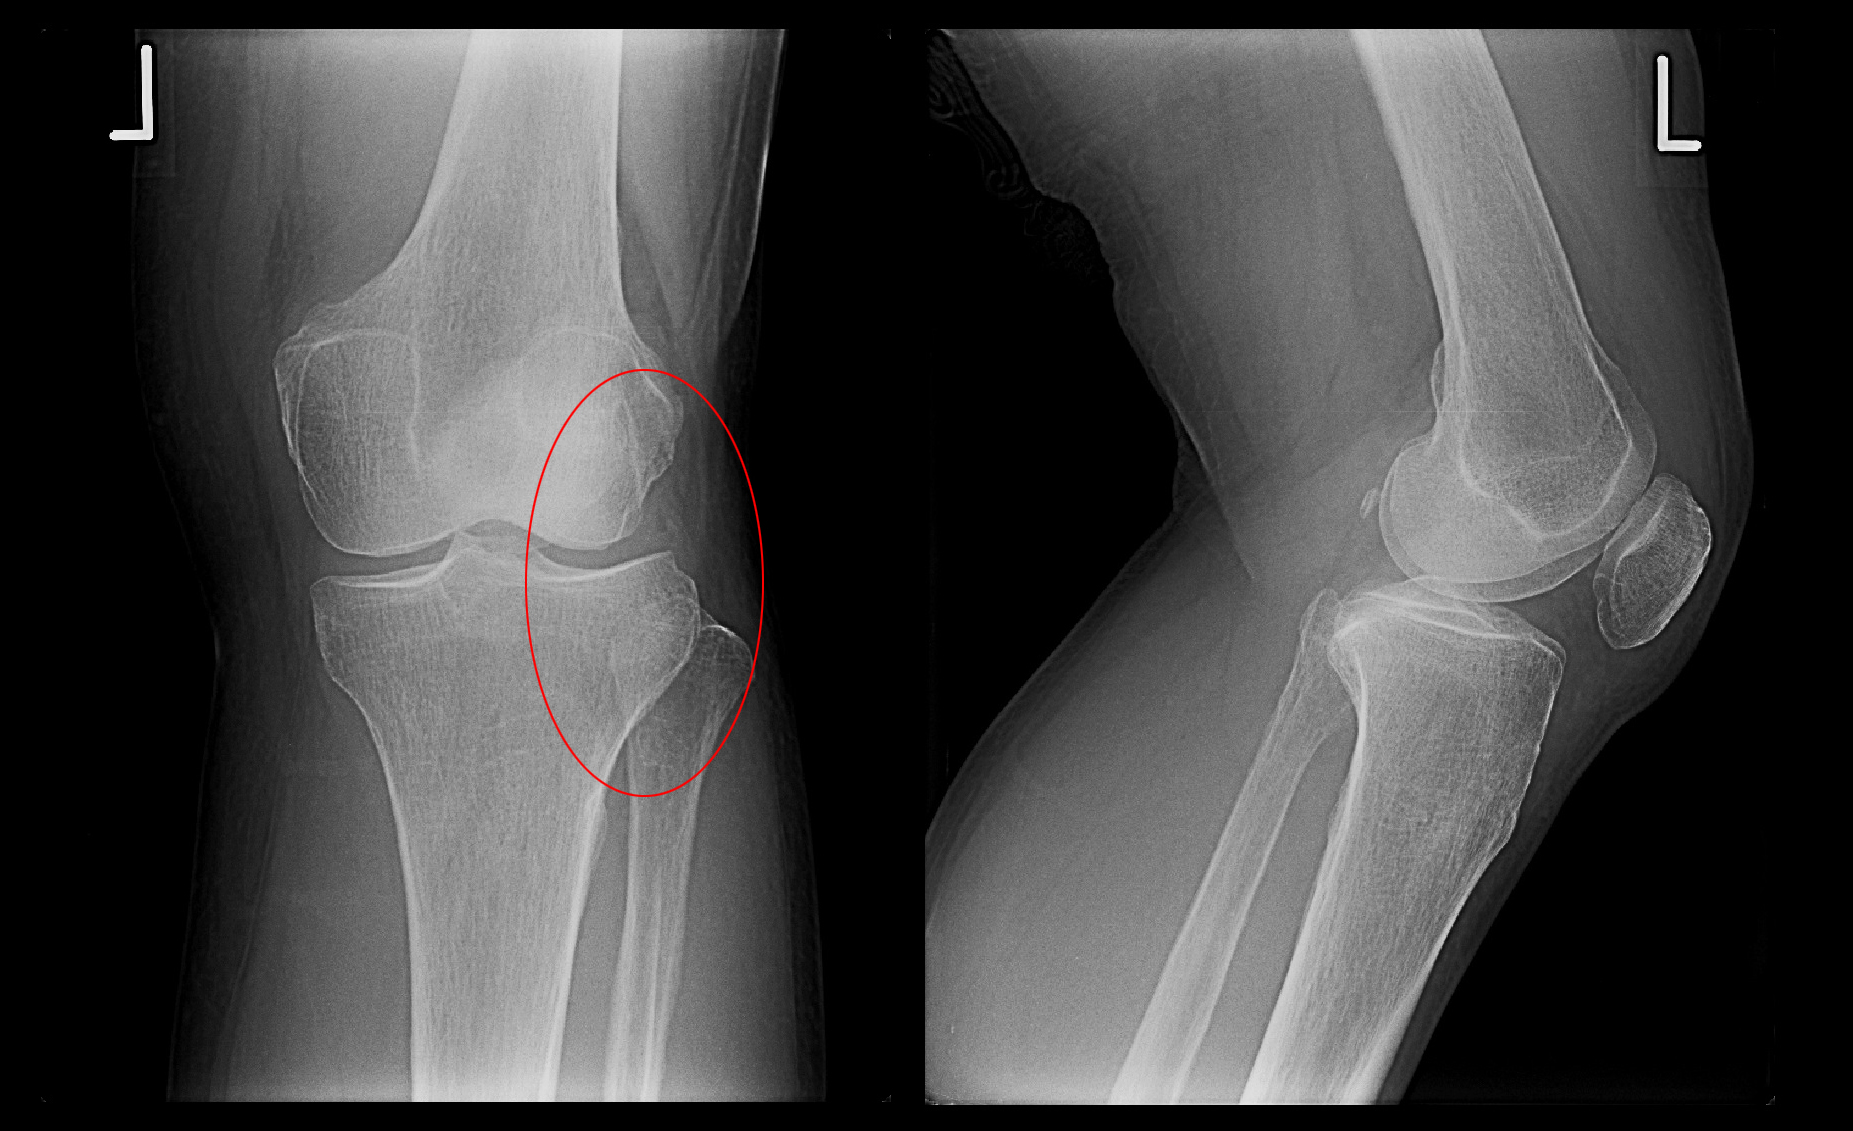

次の症例は最近の事例となります。13才の剣道をしている中学1年生のK君です。令和8年2月25日夜剣道の練習中に後方に転倒し右肘を打撲しましたが、VAS3(2:わずかに痛い、4:多少痛い)の痛みだったそうです。3日後の2月28日の練習後に右肘痛は増悪し、VAS8(とても痛い)になり、同日当院を受診されました。

13才男 Xp1.jpg

赤丸領域に痛みを訴えていました。可動域は5度から125度で軽い伸展制限を認めますが、ほぼ正常です。内側側副靭帯(赤矢印)に圧痛を認め、「K君のケガはドジャースの大谷翔平選手と同じだよ」と述べ、MRI検査を行いました。